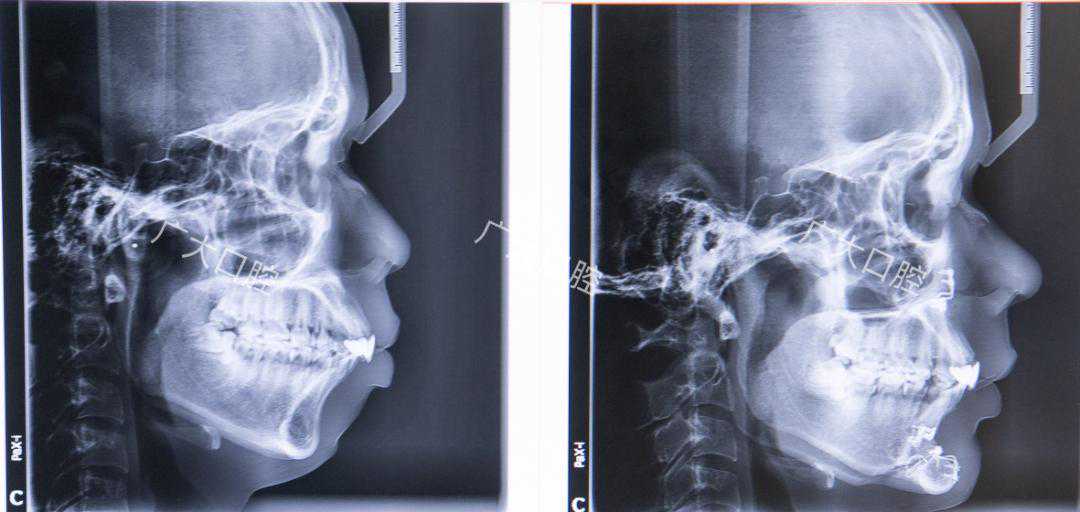

顾名思义,混合型前突就是既有牙齿突,又有骨突。多数人的嘴突都是这种类型。混合型的治疗方案,需要根据实际的牙齿情况以及头颅侧位片来定夺。

这张片子就是牙性骨性混合存在的,因为骨性程度严重,只能通过正畸+正颌手术来解决。

而有些案例虽然混合了骨性因素,但骨性程度轻,通过正畸治疗依然能取得良好的效果。根据每个人的牙性骨性比例,治疗难度和方案都会有所差异。